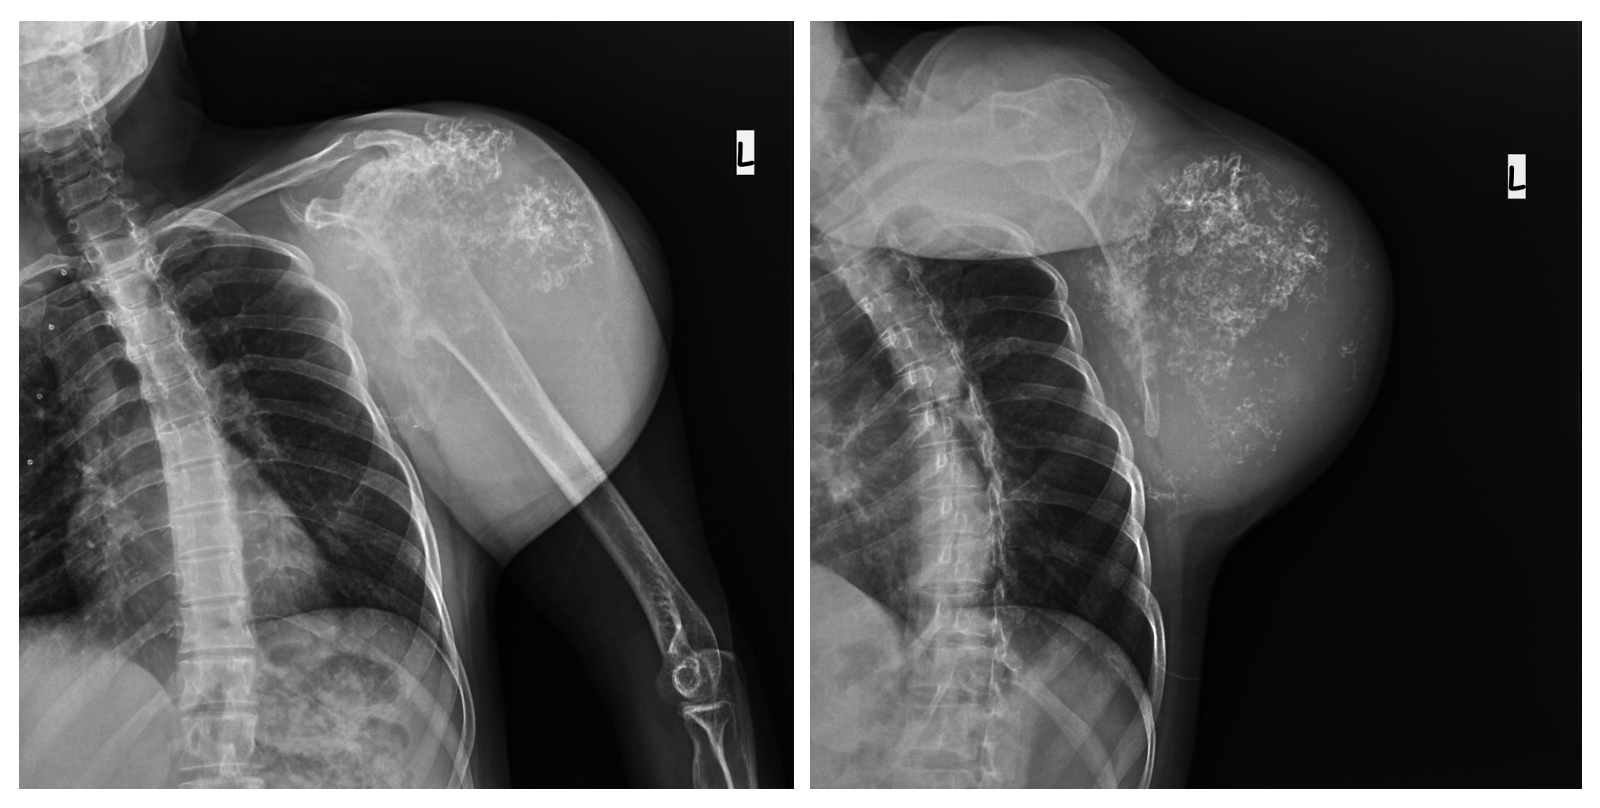

Ameliyat Öncesi: Röntgende skapula kaynaklı dev boyutlu düzensiz sınırlı kıkırdak doku içeren kitle görünmekte.

Ameliyat Sonrası: Röntgende glenoid eklem yüzü hariç totale yakın skapulektomi uygulandığı görünmekte.